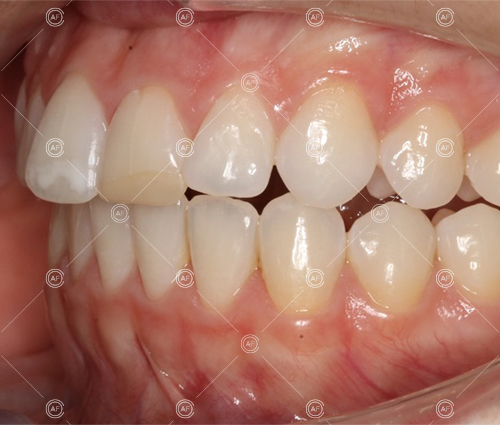

The aim of the treatment was to relieve upper and lower arch crowding, correct lower centre line shift, treat class 1 incisors and buccal segments.

Residual space from the extractions were closed using upper and lower nickel titanium closing coils. Class 2 elastics were used to facilitate space closure in order to gain class 1 buccal segments.

MH debonded in December 2020, with overall treatment time of around 14 months.